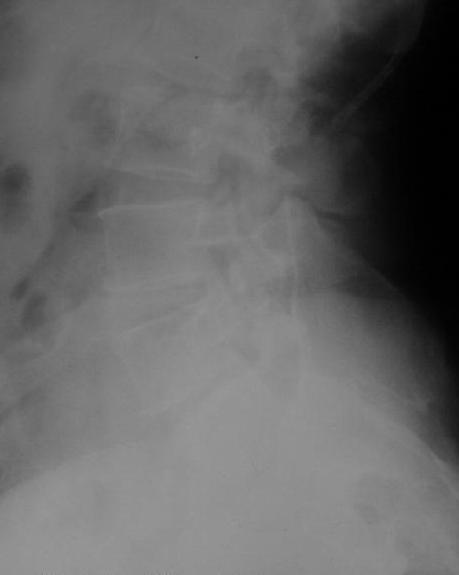

У больной 53 лет в последний год появились сильные боли в пояснице.

При обследовании выявлен анкилоз тазобедренного сустава в приведении. Видимо, в период пребывания в тяжелом состоянии появились гетеротопические оссификаты. За исключением того, что осталась одна почка, сейчас других медицинских проблем нет.

Пациентку в первую очередь беспокоят боли в спине, на отсутствие движений в суставе она вроде и не жалуется. Вопрос насчет тактики. Корсет и анальгетики вряд ли решение. Первый вариант - удаление оссификатов и эндпротезирование, второй - корригирующая остеотомия в проксимальном отделе с устранением порочного положения.

Второй вариант много проще и менее травматичен. Можно ли без размыкания сустава рассчитывать на существенное уменьшение боли за счет устранения перекоса таза?

Крайне желательно выполнить МРТ поясничного отдела, так как на представленных рентгенограммах складывается впечатление о спондилолистезе L5,котрый наиболее вероятно и является причной болевого синдрома. Кроме того у болной имеется высокий риск гнойного поражения позвоночника. Только после МРТ можно планировать коррекцию вторичной деформации позвоночника.

Снимок поясничного отдела плохо просматривается на моем компе. Нет ли там спондилолистеза L5-S1?

Учитывая отсутствие жалоб со стороны тазобедренного сустава - оперативое лечение вряд ли принесет позитивный результат. На первый план выступает спондилолизный спондилолистез (вниматльно посмотрите снимки поясничного отдела)L5 позвонка. На наш взляд больному рекомндовано выполнить транспедикулярную коррекцию и фиксацию сегментов L4-S1 с установкой кейджа в L5-S1.